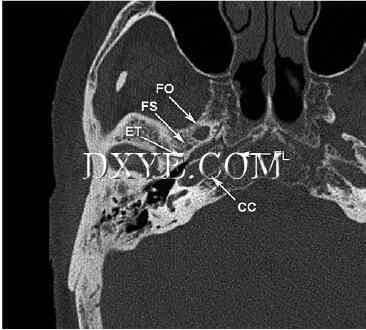

图. 3.13 轴位CT图像通过颅底各孔之间的关系表明,显示,沿中央颅底区域外侧缘管。颈内动脉通过倾斜通过颈动脉管(CC)和出口管上方软骨填充缺口,破裂孔(FL)。咽鼓管(ET)由骨和软骨段和通过内侧下方与中耳与鼻咽。注意咽鼓管之间的亲密关系,颈动脉管和棘孔(FS)。